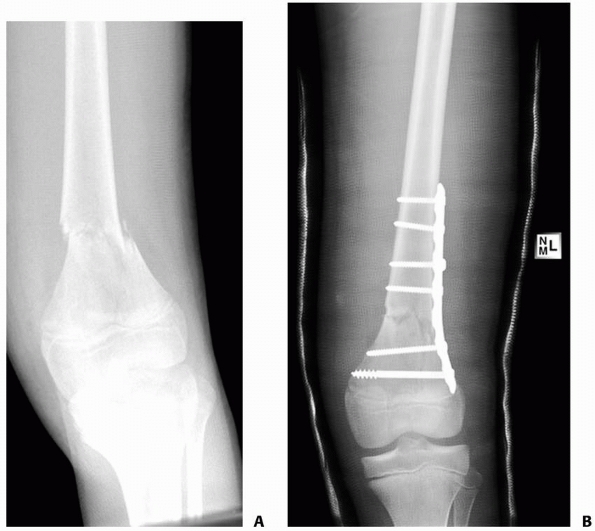

treated with intramedullary rodding, either as delayed or primary

treatment, including those caused by gunshot wounds and high-velocity

injuries.15,198

Antegrade intramedullary rod insertion maintains length, prevents

angular malunion and nonunion, and allows the patient to be rapidly

mobilized and discharged from the hospital. However, other techniques